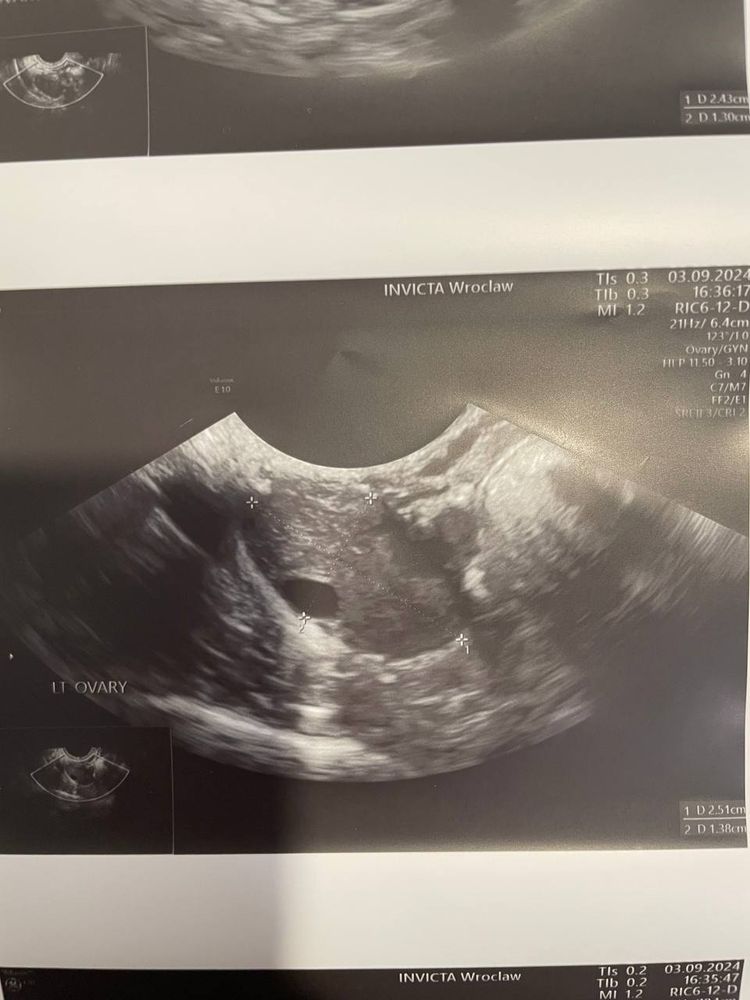

В левом яичнике образование небольшое , возможно желтое тело с прошлого цикла не ушло . Нужно в идеале повторить узи

Ну на правом яичнике видно какие то черные пятна, похожи на фолликулы. На левом вот это одно большое, непонятно какого размера, может фолликул, может киста с прошлого цикла. И мелкие черные пятна если приглядеться по краю яичника - это фолликулы